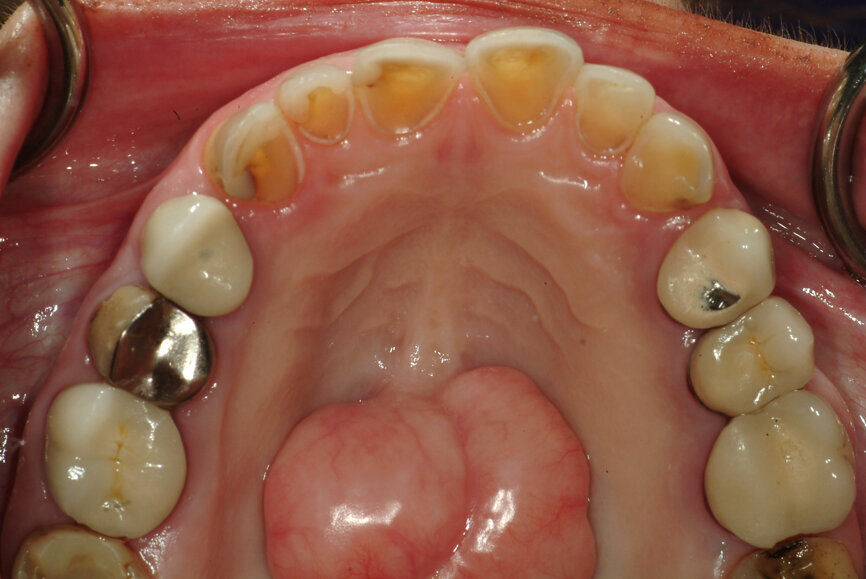

Fig. 13: Intercuspation requiring opening of the vertical dimension for restorative space.

Fig. 14: Significant wear requiring occlusal coverage and altering

of occlusion.